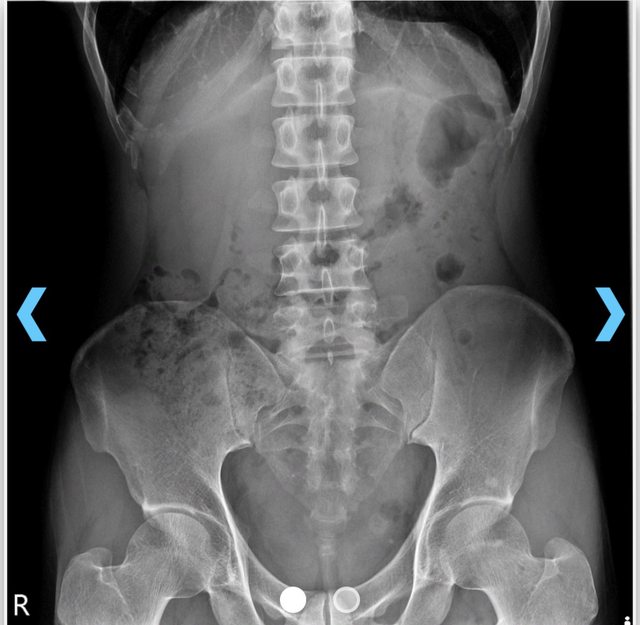

5/26週日打完羽球後,覺得下背腰椎有點不適,但是還是可以正常生活。 5/27晚上突然覺得右側屁股很痛,刺痛感,右腳腳掌麻,右腳小腿無力,整晚痛到無法入 眠。 5/28早上去診所打針加吃藥後,隔天下背疼痛恢復正常,右腳掌一樣麻,右腳無法單腳墊 腳,走路超過一分鐘就會右側屁股很痛(刺痛)及右腳小腿酸痛無力,坐著及躺著都沒事 。 5/31早上到關渡醫院看骨科,照了兩張X光片,醫生無法確定原因,開了21天的消炎止痛 藥後,要我21天後回診再看看。 5/31下午到天母力康診所看,醫生看了關渡醫院的x光片後,做了一些動作測試,說明有 可能是椎間盤的問題,便去旁邊復健做熱敷電療及拉背了。 6/5早上到馬偕看神經外科,醫生說已經從腰椎影響到腳掌,算是很嚴重,有可能是椎間 盤破裂,要開刀,然後拍了兩張不同姿勢的x光片跟預約兩週後做神經傳導測試,到時再 看需不需要做核磁共振。 6/5下午到誠星給李思瀚治療師看,做了一連串的測試,李老師認為椎間盤的問題機率比 較大,做了很多放鬆神經緊繃的動作,最後建議可以去做增生療法紓緩疼痛。 目前我的症狀一直都沒改善,右腳掌一直保持麻麻的感覺,右腳小腿無力,站起來走路一 兩分鐘右側屁股會非常疼痛刺痛,右小腿會很緊繃痠痛,根本也無法上班,馬偕醫院每次 的回診都要再等一個禮拜,下週回診看x光片,下下週做肌電圖跟神經傳導,每天走路的 疼痛及無法上班,實在沒辦法一直等下去了,請問有人有類似的經驗嗎?或是有推薦的醫 師呢?謝謝 附上關渡醫院拍的x光片 https://i.imgur.com/55QCqYC.jpeg

capybaradash: 其實看第一張就知道你骨盆一高一低+順時針旋轉了 06/07 10:05

capybaradash: 大概率有長短腳,但不確定是功能性還是實際上的 06/07 10:07

capybaradash: 左長右短 06/07 10:07

capybaradash: 換個腳度想,你如果實際上雙腳等長,但是你右邊骨 06/07 10:56

capybaradash: 盆順時又離地更近,這走路右腳一瞪會痛也就不奇怪 06/07 10:56

capybaradash: 了 06/07 10:56